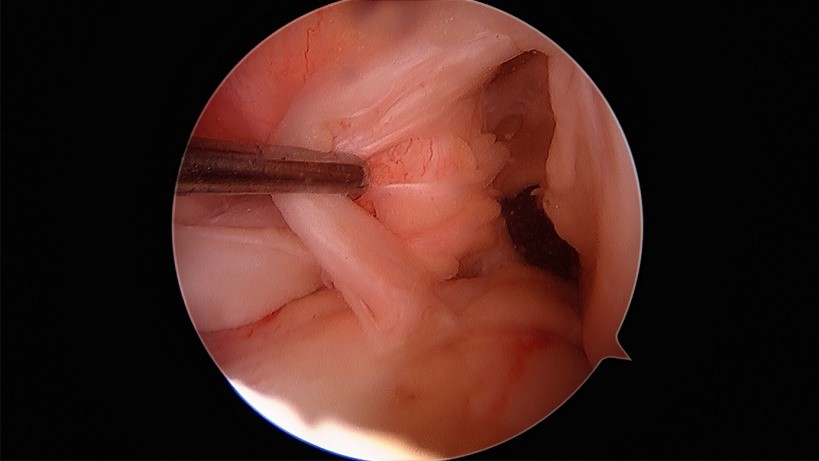

損傷後の弱々しい前十字靭帯

移植腱の設置後